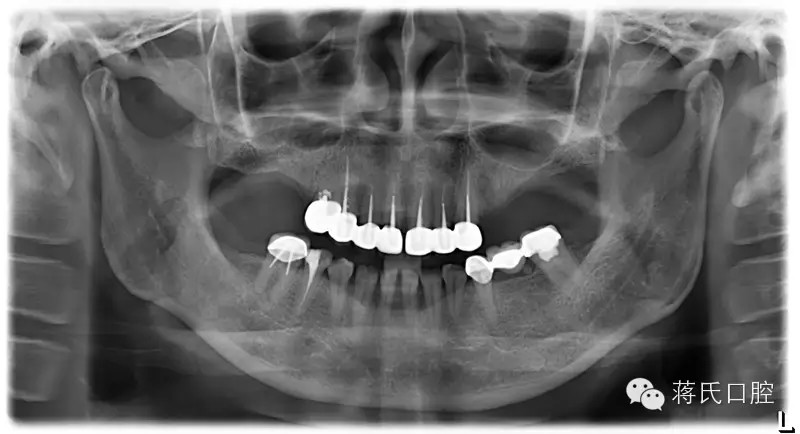

患者情況 女 49歲 ,三類骨,右上區(qū)骨高度6毫米, 寬度8毫米。左上區(qū)骨最低點1毫米,寬度3毫米

種植前X線,左側(cè)外提升右側(cè)內(nèi)提升